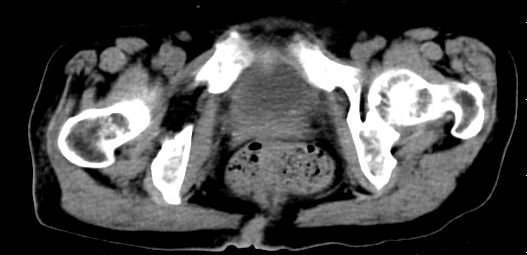

标题: CT10133:F、74岁,反复血尿10天。 [打印本页]

标题: CT10133:F、74岁,反复血尿10天。

考虑膀胱癌可能性大伴双侧输尿管下端扩张.

2.双侧输尿管下段扩张.

2.双侧输尿管下段扩张.输屎管结石可能大。建议作进一步检查。

双侧输尿管下端扩张,并膀胱内血凝块 输尿管下端结石